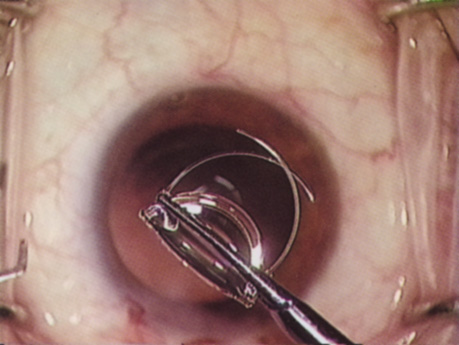

A mature cataract precludes visualization of the fundus. A B-scan ultrasonographic examination provides a real-time, two-dimensional (2D), cross-sectional image of the globe along the marked axis of the probe (Fig. 3). Cataracts are more common in patients with chronic retinal detachment, prior trauma, or intraocular tumors; therefore, a B-scan study is helpful in excluding structural posterior segment pathology before surgery on a mature cataract. Although a negative result to B-scan evaluation is reassuring, the surgeon should remember that it does not predict postoperative visual outcome. The B-scan can be thought of as a picture of Cincinnati from an airplane; the office buildings may all be standing, but you cannot tell whether the people in them are working.